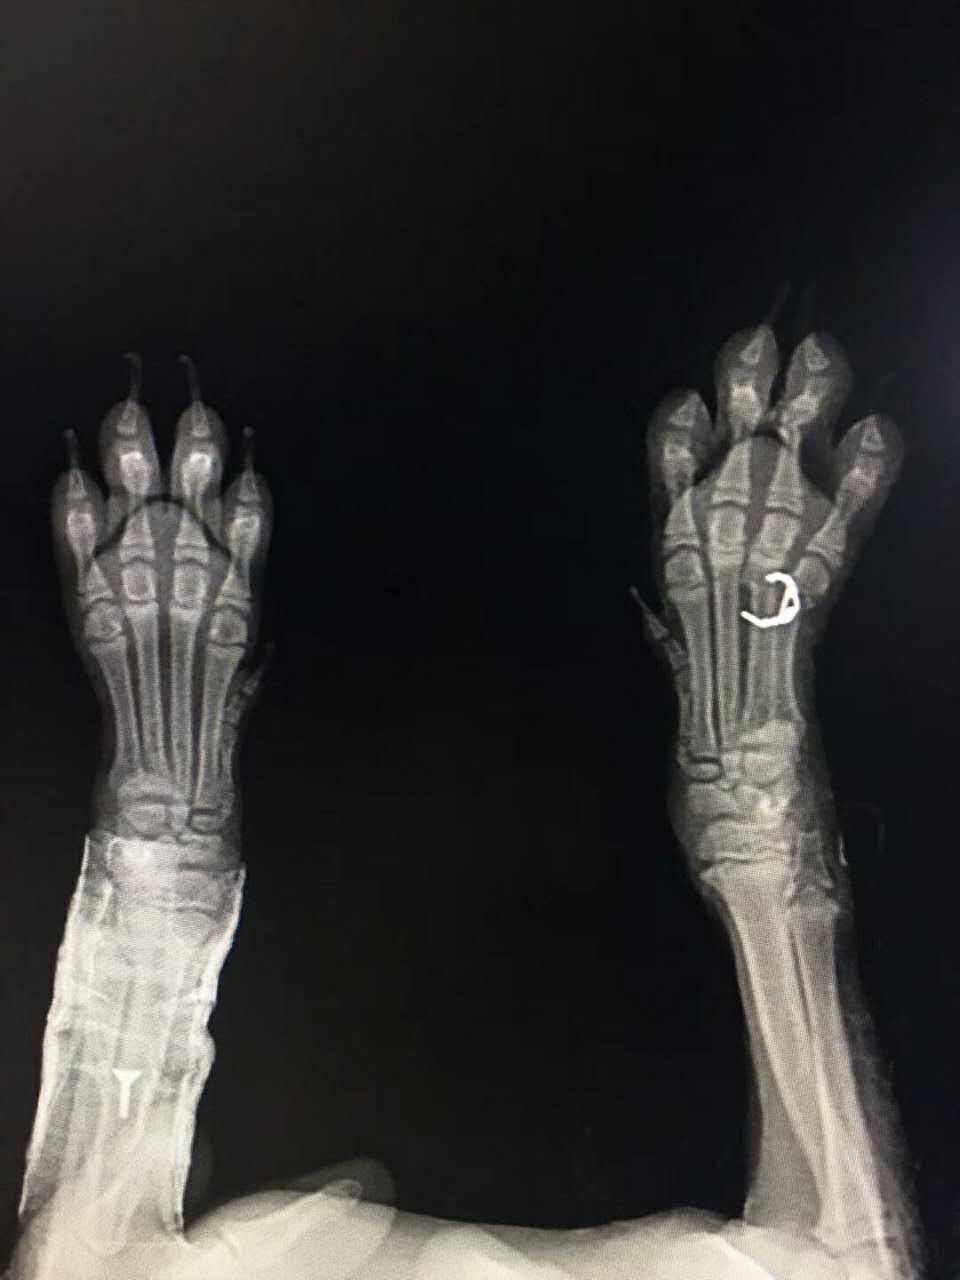

掌骨骨折內(nèi)固定術(shù)

掌骨骨折內(nèi)固定術(shù):比熊,開心,4月齡,從高處跌落,造成右前肢掌骨骨折,實(shí)施內(nèi)固定手術(shù),正在恢復(fù)中......